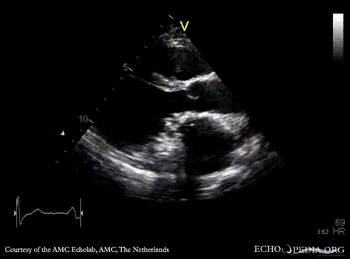

Mechanical mitral valve prosthesis

Courtesy of: AMC Echolab, AMC, The Netherlands

PLAX: mechanical mitral valve prosthesis, dilated left ventricle and left atrium PLAX with Color Dopler: no mitral regurgitation